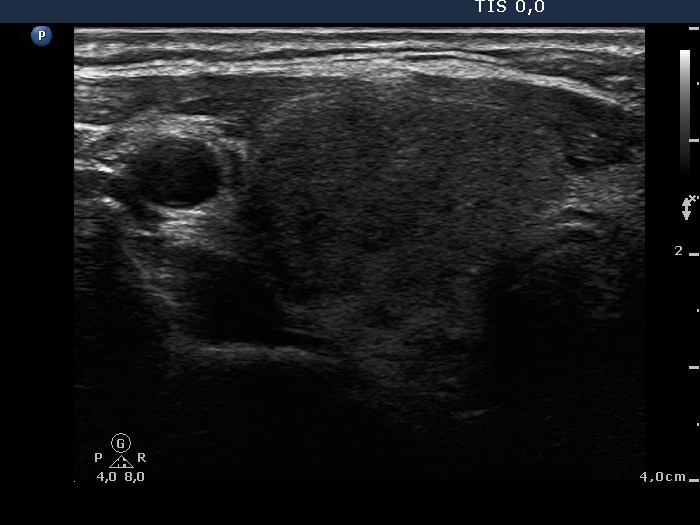

Ultrasonography: There were many hypoechogenic areas with blurred borders within both lobes. The vascularization was decreased.